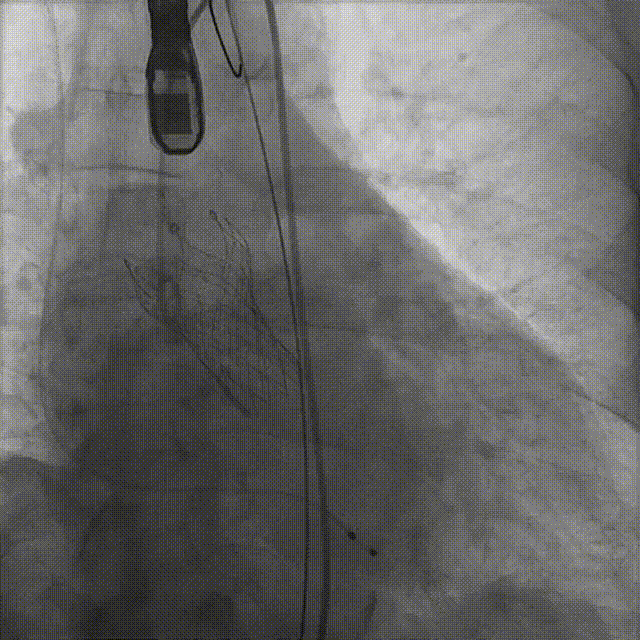

患者病史 体检发现心脏瓣膜病半月余,平素无症状 ,有高血压病史。 后来院复查诊断为:主动脉瓣狭窄(重度)、先天性主动脉瓣二叶瓣畸形、心室肥厚、升主动脉扩张心功能 I 级(NYHA 分级)、高血压病 2 级(极高危)。 术前 CT:Type0型二叶瓣,瓣叶增厚,无钙化,类风湿性;瓣环径25.6mm,LVOT稍收窄,瓣环水平夹角66.6°,轻微横位心;左右冠开口高度可,瓣叶不长,无冠脉风险;心室收缩末内径约32mm,室壁增厚;外周入路无明显迂曲,无钙化、双侧内径可、双股中分叉,右侧为主入路能够支持20F大鞘通过。 造影角度及入路:LAO 6° CAU 13° 手术策略 采用右侧股动脉为主入路,左侧为辅助入路,常规穿刺。推荐使用20球囊预扩,预装TAV29瓣膜,初始定位对齐瓣环上0mm开始释放。 手术过程 20号球囊预扩无明显腰征 输送器过弓跨瓣顺滑 80%工作位观察 术后造影,瓣膜释放位置良好,无瓣周漏 术后超声:人工生物瓣释放后形态满意,瓣叶开放、关闭活动良好,无瓣周漏;跨瓣血流速度降至 2.5m/s,平均压力梯度6mmHg,符合手术预期。 Prostyle A®预装干瓣——“刚柔并济”助力临床最优化解决方案: 丝滑过弓能力:Prostyle A®短瓣架设计联合远端超滑亲水涂层,即使没有联合使用snare,都可以柔顺过弓,该例横位心的患者更好的展现了输送系统的柔顺性; 平衡的径向支撑力:该例患者Type0型二叶瓣,术后形态展开良好且无瓣周漏,在横位心等复杂情况下实现稳定锚定。 80%可回收设计:80%工作位观察,起搏时间更短,对患者损伤减少到最小,也利于术中精准调整瓣膜位置,保证术后效果。